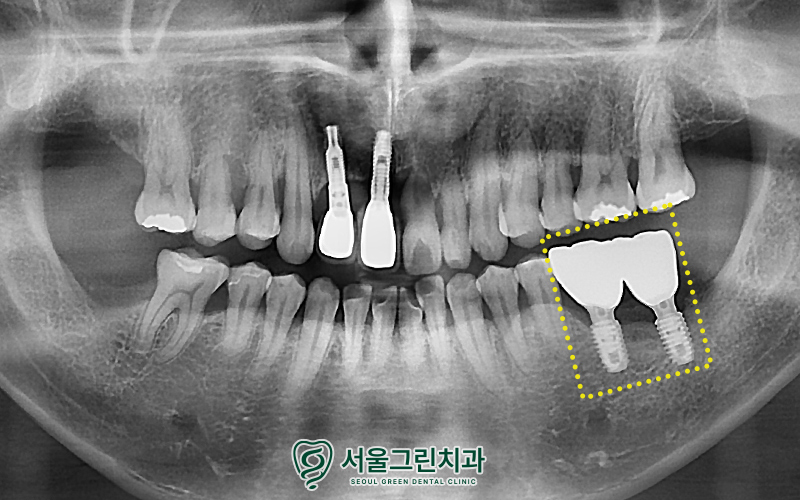

잇몸뼈에 잘 고정된것을 확인하고,

크라운(보철물)까지

안정적으로 셋팅해드린 모습입니다!

치료가 마무리 된 이후

정기검진과 더불어

본원에서 이루어지는 치주관리로

임플란트를 꾸준하게 잘 사용하고 있으며